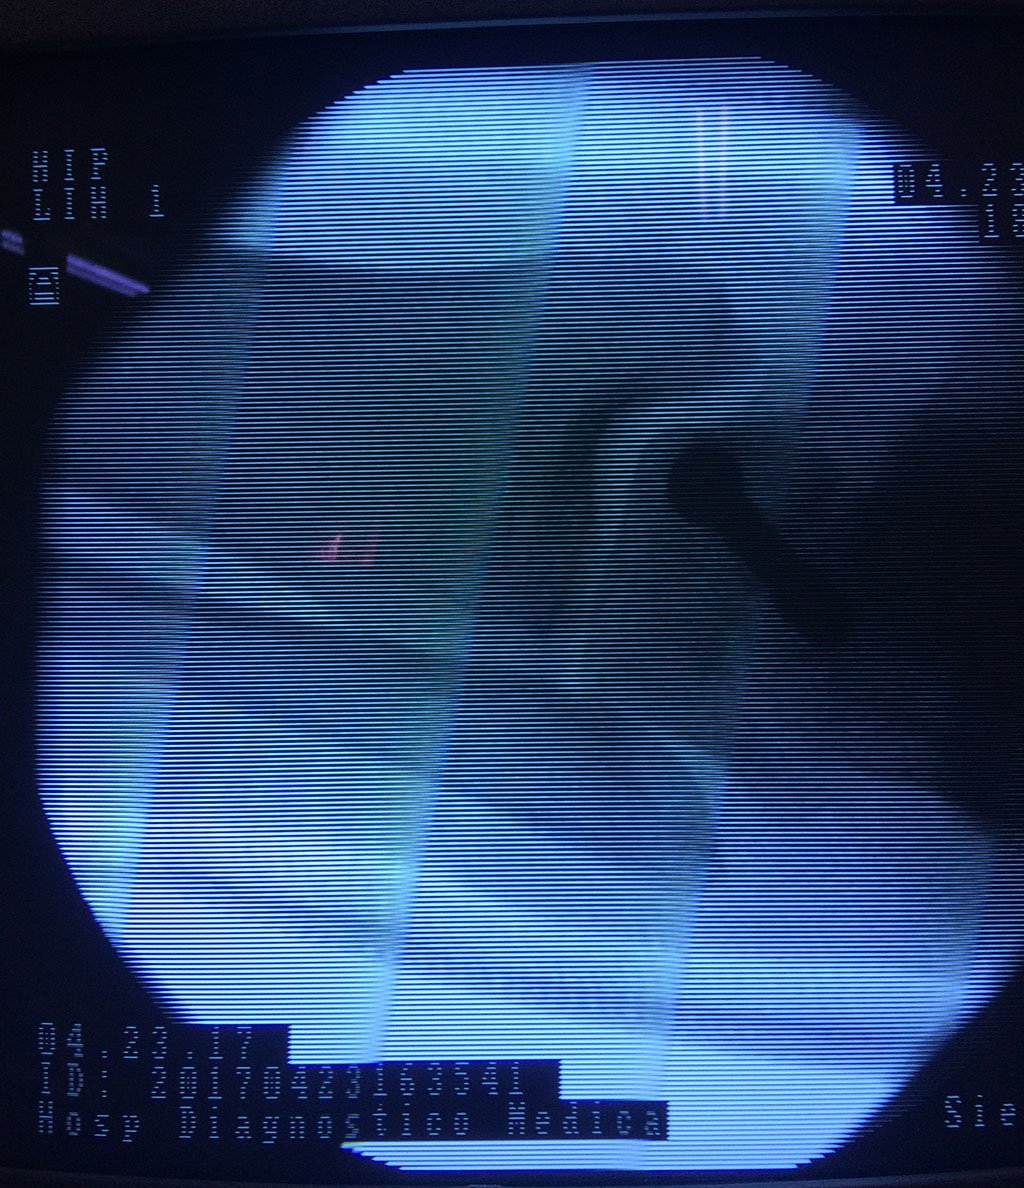

Cuando se necesita cirugía, es probable que esta implique el uso de clavijas de metal, tornillos o placas para sostener los huesos en su lugar mientras la fractura se consolida. Los elementos de soporte pueden ser temporales o permanentes.